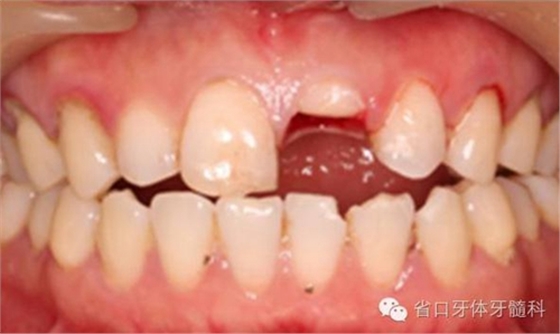

圖4. 拔除斷冠后的唇面照片

圖5. 拔除斷冠后的發(fā)現(xiàn)腭側(cè)斷面及齦下約3毫米